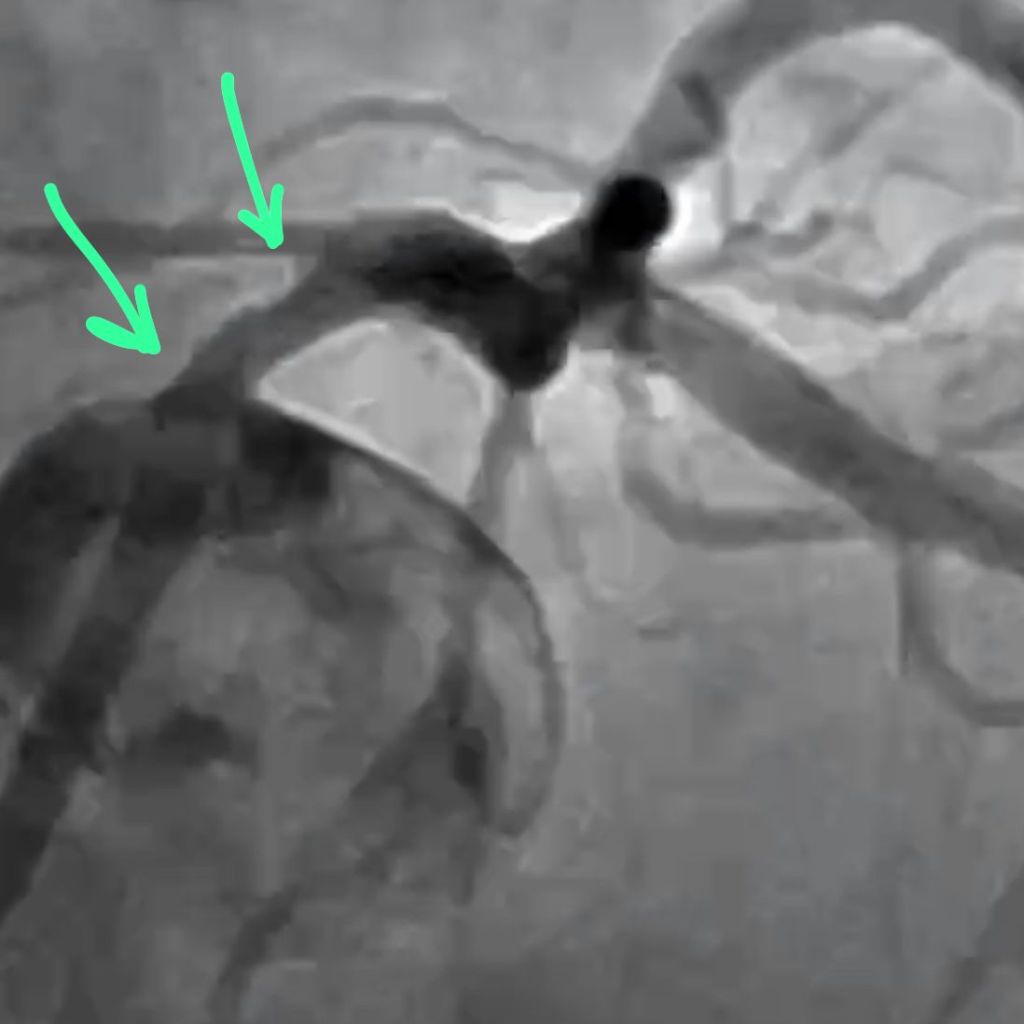

A. Functional last conduit because the RCA is critical. The entire body of the LM is involved. Heavy calcium is an understatement.

B. Medina 1,1,1 – both arteries need to be addressed. Our plan was to perform DK crush.

I am going to share a series of still frames that shows the changing morphology of the LM lumen. This is baseline.